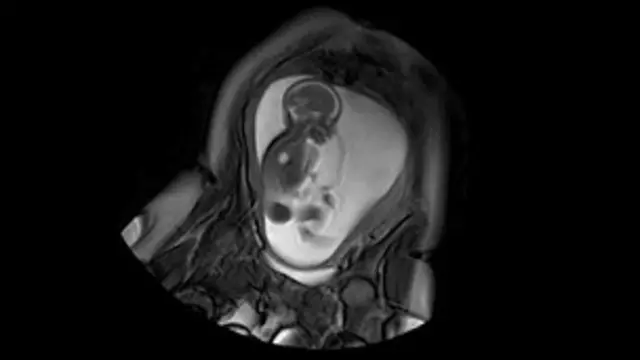

Um livro recém-lançado por um neurologista sugere que o estresse na gravidez elevaria as chances de uma criança nascer gay.

Segundo o holandês Dick Frans Swaab, autor de We are our Brains (Spiegel & Grau, 448 páginas) ("Nós somos os nossos cérebros", em tradução livre), a homossexualidade estaria ligada a uma mudança na composição hormonal e na formação do cérebro.

Nesse sentido, o neurologista acredita que fumar ou ingerir drogas na gravidez pode influenciar na formação da sexualidade do feto.

"Mulheres grávidas que sofram de estresse tem maior chance de darem a luz a bebês homossexuais, porque os níveis elevados do hormônio de estresse cortisol afeta a produção de hormônios sexuais fetais", escreve Swaab.

A abordagem de Swaab, professor emérito de neurobiologia da Universidade de Amsterdã, parte do pressuposto de que a sexualidade é determinada no útero e não pode ser alterada, contrariando uma visão partilhada por outros especialistas de que a orientação sexual é uma escolha individual.